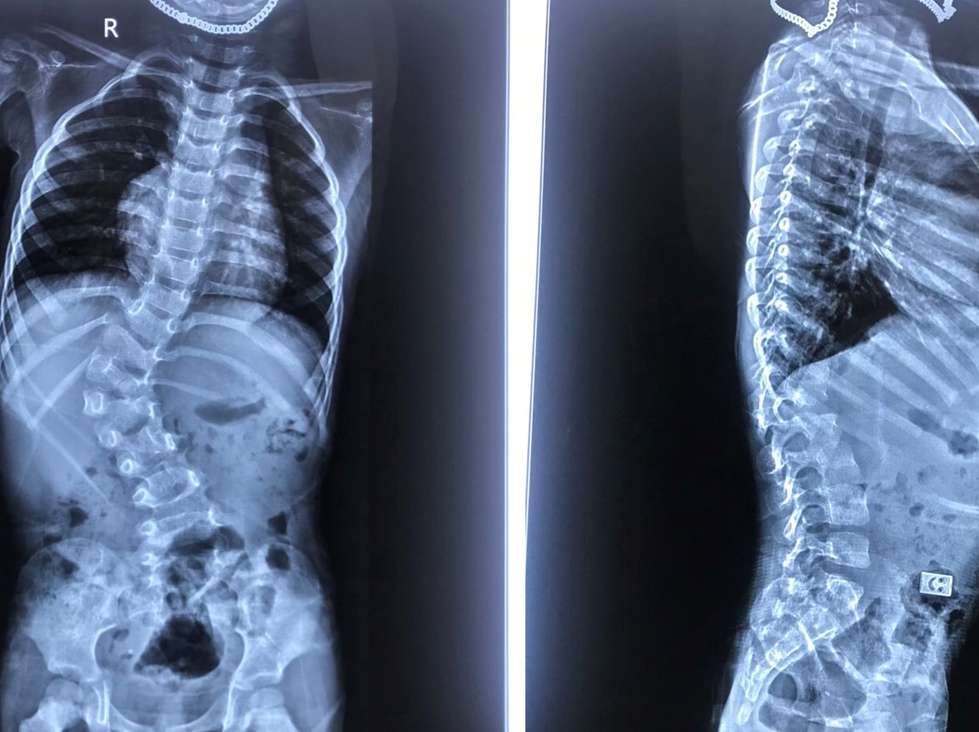

Chụp X-quang thường có thể xác định chẩn đoán chứng vẹo cột sống và biết được mức độ nghiêm trọng của độ cong cột sống. Bệnh nhân được chẩn đoán bị cong vẹo cột sống khi cột sống cong sang phải hoặc trái với góc Cobb đo trên phim chụp X-quang > 10o.

Lựa chọn phương pháp điều trị cong vẹo cột sống tùy thuộc vào mức độ nghiêm trọng của đường cong. Trẻ em bị cong vẹo mức độ nhẹ (góc Cobb > 20o) thường không cần điều trị, nhưng cần kiểm tra sức khỏe thường xuyên để theo dõi tình trạng có xấu đi khi lớn lên hay không.

Nẹp xương

Nếu xương trẻ em vẫn đang phát triển và trẻ bị vẹo cột sống mức độ trung bình (góc Cobb từ 20 – 40o), bác sĩ có thể đề nghị mang nẹp. Mang nẹp không chữa được cong vẹo cột sống, nhưng nó thường ngăn tình trạng trở nên tồi tệ hơn.

Chứng vẹo cột sống nặng thường tiến triển theo thời gian, vì vậy bác sĩ có thể đề nghị phẫu thuật để giúp làm thẳng đoạn xương sống bị vẹo.